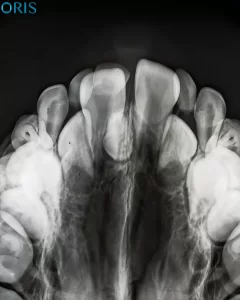

ما هي حالة فرط عدد الأسنان (Hyperdontia)

ما هي حالة فرط عدد الأسنان (Hyperdontia)؟ فرط عدد الأسنان هو مصطلح طبي يُستخدم عندما تنمو أسنان إضافية لدى الشخص بجانب الأسنان الأساسية سواء كانت